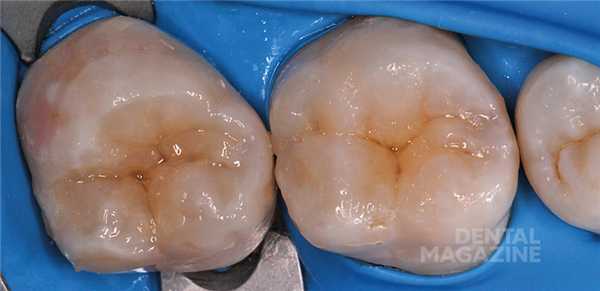

Для предупреждения возможного склеивания следует нанести на поверхность силикона небольшое количество адгезива. Ключ накладывается на зуб и медленно прижимается. После того как силиконовый оттиск встанет на свое место, нужно медленно его снять легкими раскачивающими движениями. Не следует торопиться и пытаться извлечь ключ одним рывком: это приведет к деформации композитного материала. Если все сделано правильно, порция неотвержденного эмалевого композита должна принять точную форму исходной жевательной поверхности (рис. 8) .

Излишки пломбировочного материала легко убираются брашиком. При возникновении каких-либо деформаций допускается повторная установка ключа. Далее проводится полимеризация в течение 30—40 секунд с учетом толщины композитного слоя (рис. 9) .